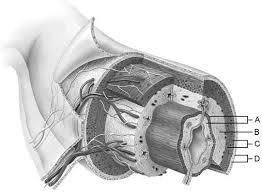

Mucosa

A

Duodenal glands found here

B

Smooth muscle layer.

C

Serosa.

D

Area of the lamina propria

A